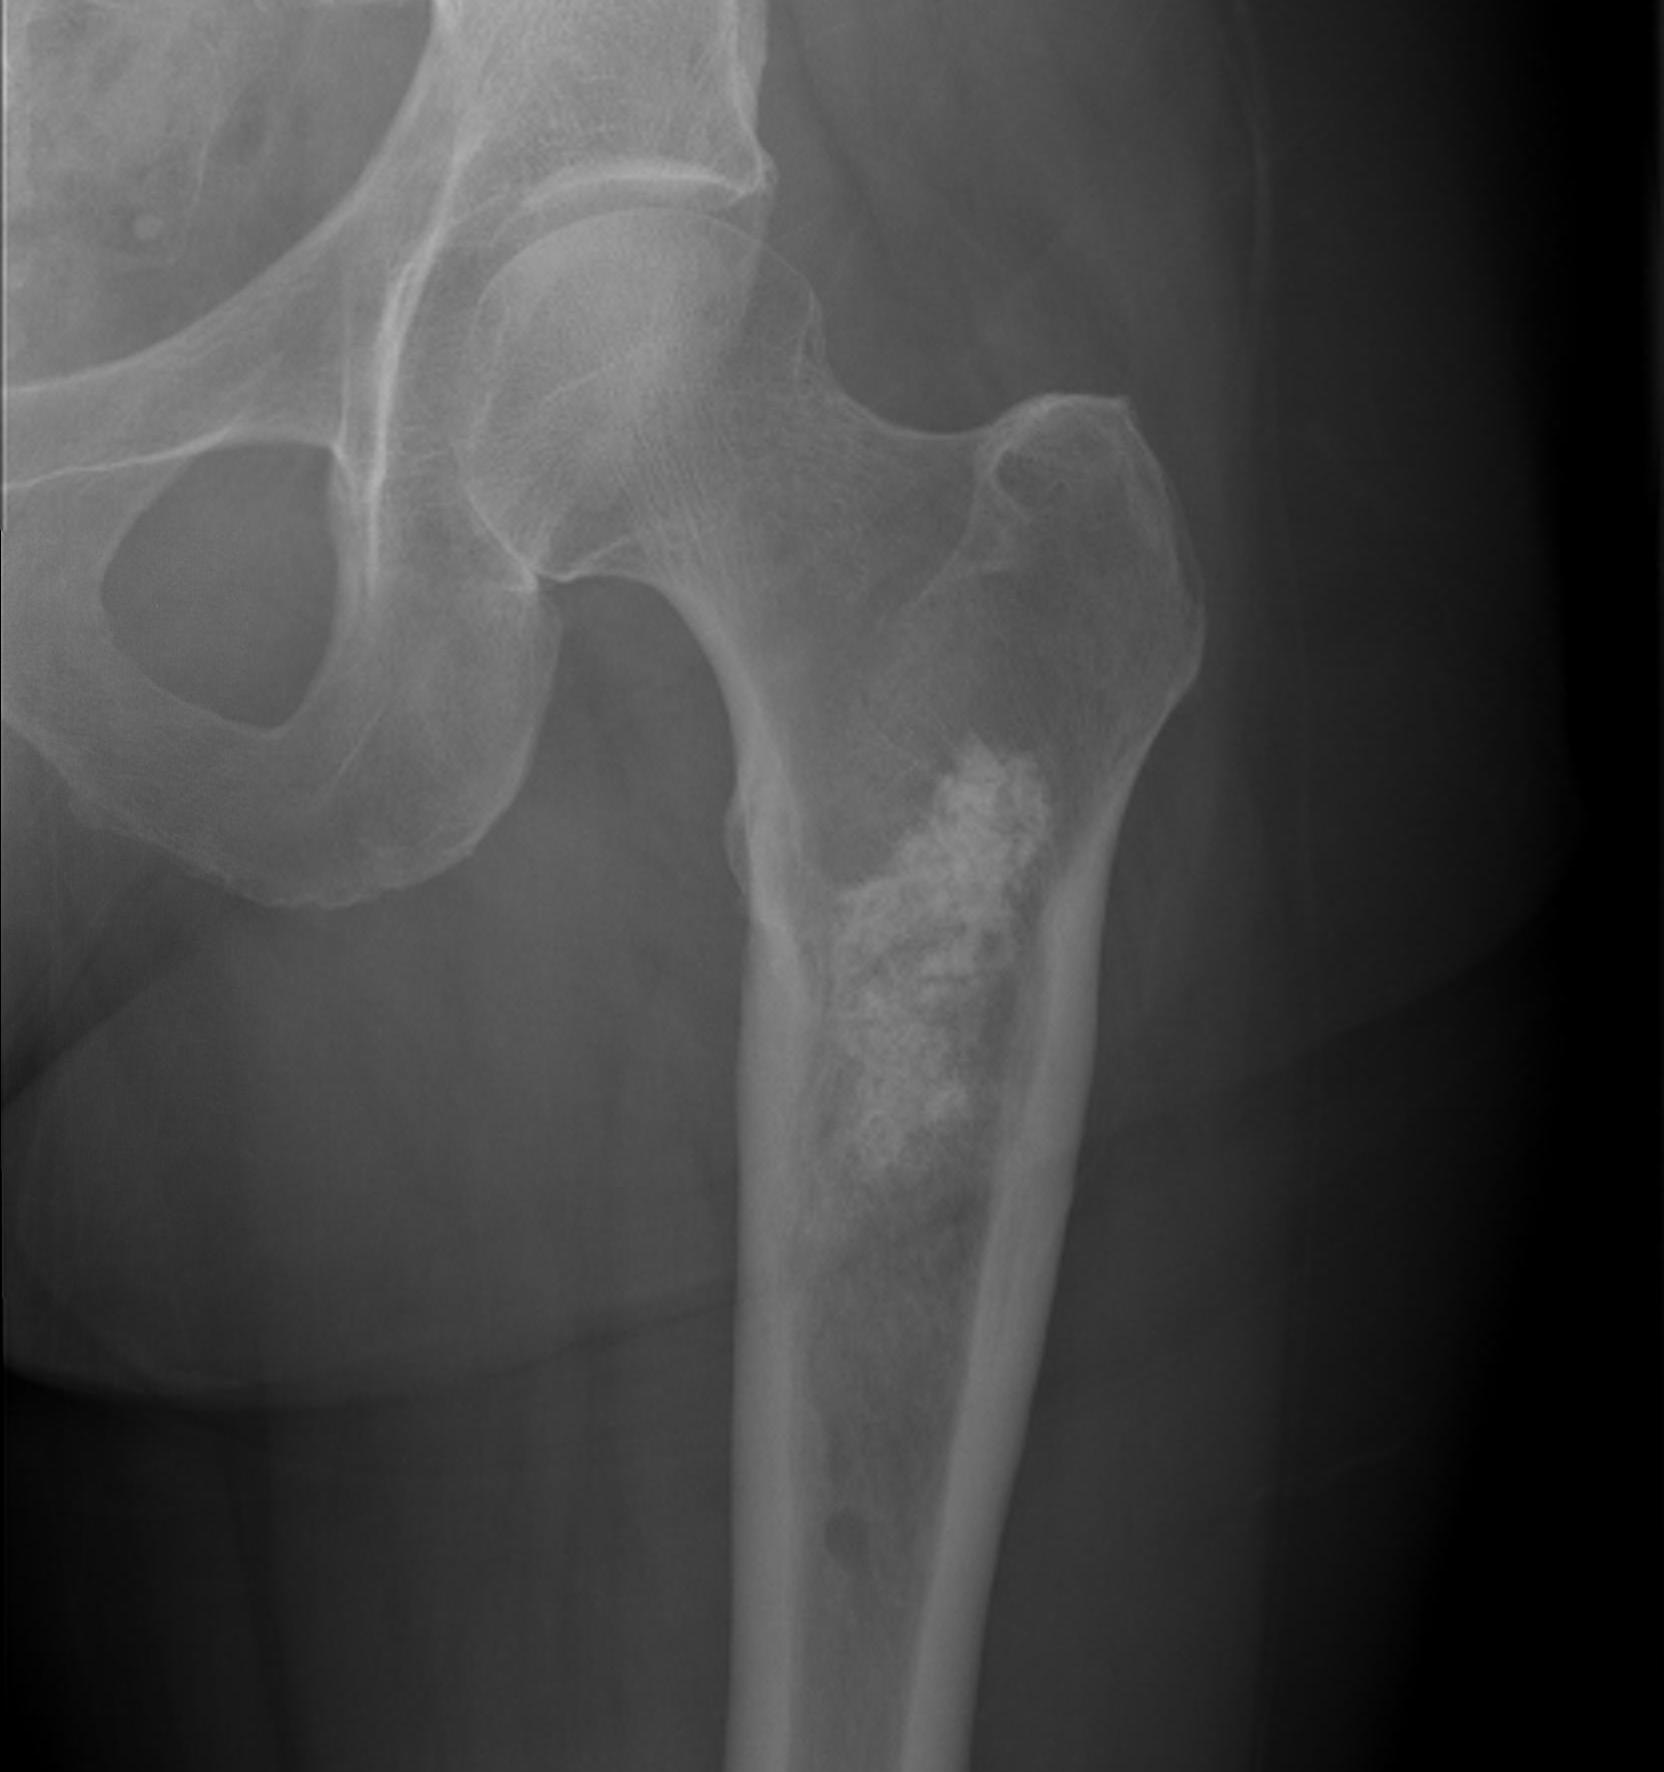

2. Subtrochanteric / femoral shaft

- lateral approach

- aim anterior or posterior to lateral intermuscular septum depending on compartment

- avoid rectus femoris / vastus intermedius

- ok to resect part of vastus lateralis or biceps femoris